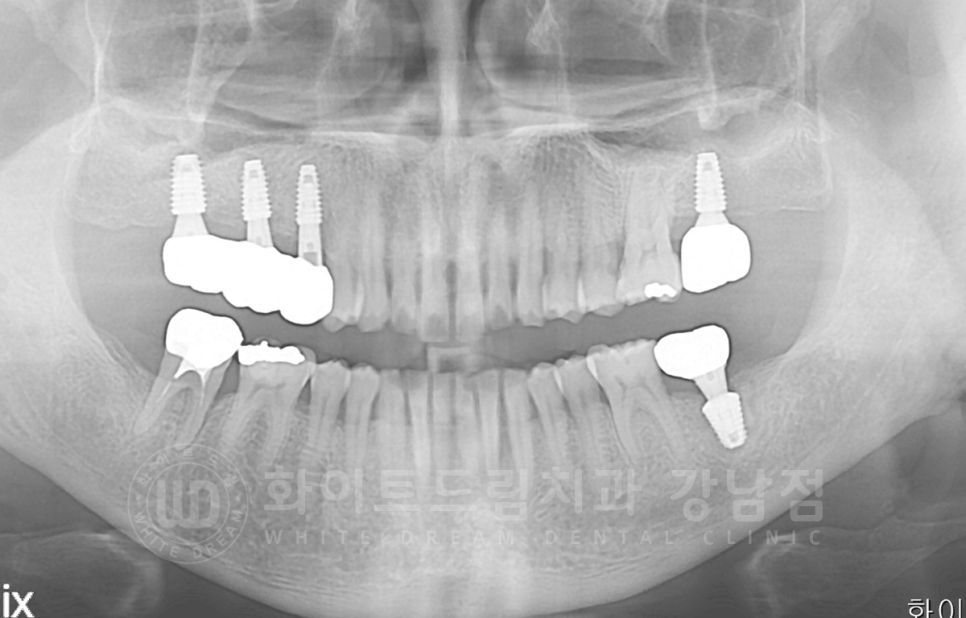

식립 후 x-ray 사진입니다.

▲ 임플란트가 식립 된 부위에 볼록하게 뼈이식이 진행된 것이 보이실 겁니다.

상악 어금니 임플란트 총 치료 기간 : 16.06.03 - 17.09.29

서초동 어금니 임플란트 / 강남역 화이트드림치과